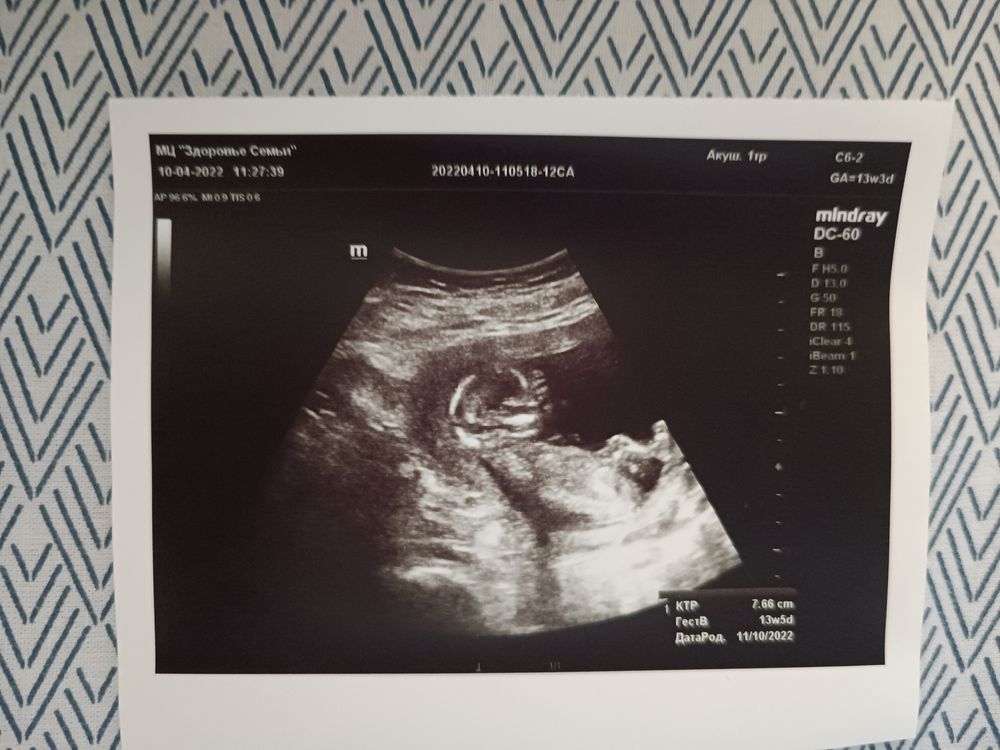

10-ое апреля - очень волнительный день, мы дождались первого скринига. В процессе УЗИ нам сообщают, что будет мальчик (вот эта новость нисколько не обрадовала), абсолютно здоровый мальчик. Пару дней ушло на то, что принять пол ребенка, зато дальше беременность протекала совершенно спокойно и легко, и нервы трепал только капитальный ремонт в нашей новой квартире, который шел с октября 2021-го года.